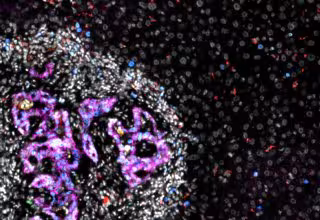

Metástasis de cáncer colorrectal (mitad izquierda de la imagen) en el hígado. Células de cáncer colorrectal, en color magenta, rodeadas de otras células, en blanco, dentro de la metástasis (imagen de microscopio).

Metástasis de cáncer colorrectal (mitad izquierda de la imagen) en el hígado. Células de cáncer colorrectal, en color magenta, rodeadas de otras células, en blanco, dentro de la metástasis (imagen de microscopio). - ETH ZURICH / MORGAN ROBERTS, ELENA GUIDO VINZONI